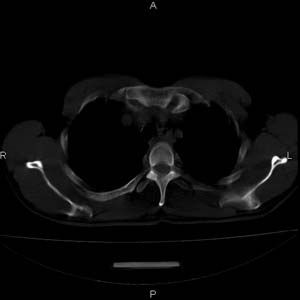

患者男,50岁,在高速公路上发生车祸来查头颅及胸部。查体双下肢感觉障碍。我看着好象气管有异物且有一个胸椎有骨折,但椎周软组织不对劲,请大家看看。

上传骨窗及肺窗 不然不好定骨折,双侧胸腔少量积血。

考虑1:椎旁血肿,2:tb

结合病史考虑胸椎挫伤及椎旁血肿,右下肺挫伤.建议mri.

双侧胸腔少量积血,t4-5椎旁软组织肿胀。

结合病史考虑胸椎挫伤及椎旁血肿,右下肺挫伤.建议mri

结合病史考虑胸椎挫伤及椎旁血肿。随访复查吧,有的病人会发生迟发性椎体压缩骨折。